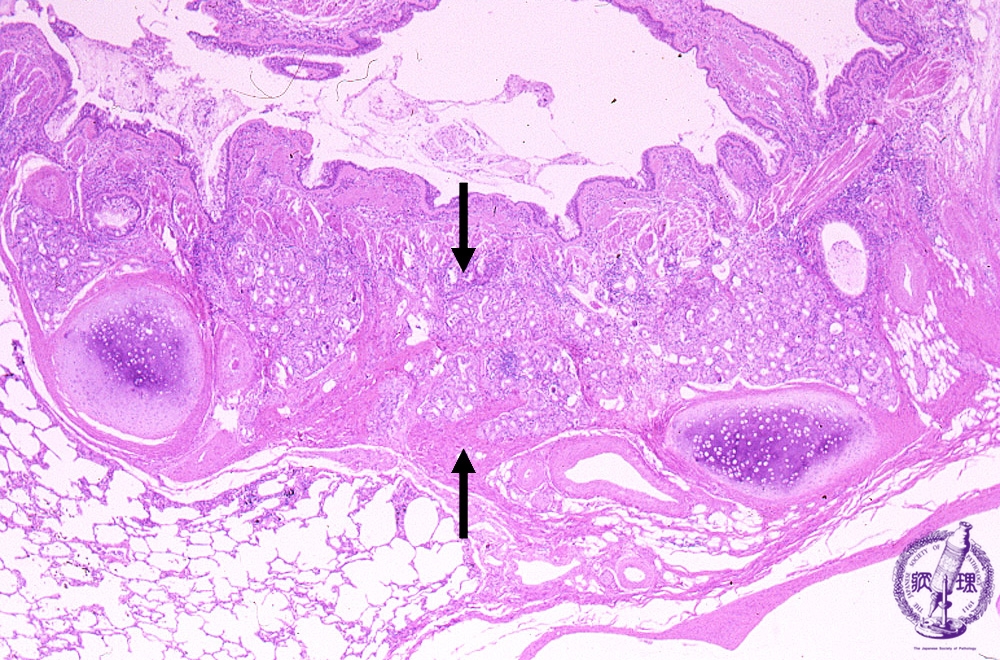

Microscopic view (HE stain, low power view): Bronchial glands are hyperplastic.

Click the image to see the enlarged image.